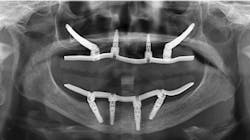

This next situation is a very common one when observing the current trend to oppose zirconia restorations on two edentulous arches without meticulous and knowledgeable occlusal equilibration. This can cause an implant or two to take the entire occlusal load, causing undue forces and stress on theAfter many decades of prosthodontic practice and hundreds of rehabs, I have found this an almost impossible and threatening technique. There is no articulator that can consistently mimic patient occlusion. Definitive occlusal equilibration is mandatory at seating, after a few weeks in the mouth, and subsequently on recare appointments (figures 4–6).